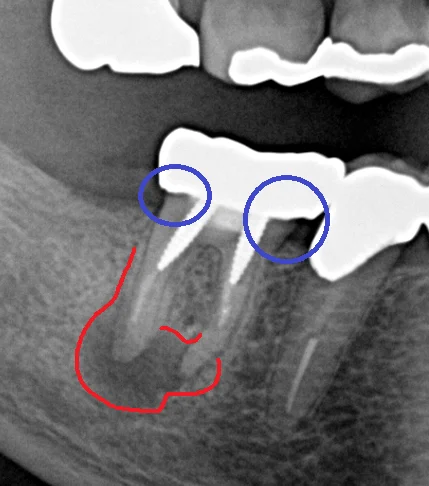

まず青丸の部分ですが、入っているクラウンの適合があまり良くなく、通常の歯よりも大きく膨らんだ形の被せ物が入っています。 こういった形態の補綴物を入れると被せ物と歯の間が磨きづらく・・・

虫歯になったり歯周病になりやすくなります。

根の方には大きなネジのような土台が2本入っているのですが、非常に歯の壁ギリギリの所に入っているため、この時点で患者さんにはパーフォレーションを起こしてしまっている可能性が高いことを説明しました。

赤丸の所に非常に大きく膿が溜まっています。サイズ的には歯の全長の1/3~1/2程度ですので、歯科医師によっては抜歯を視野に入れる状態かと思います。

恐らく前の先生は「膿が大きいと抜かなければならない」という考えの方だったのかと思います。